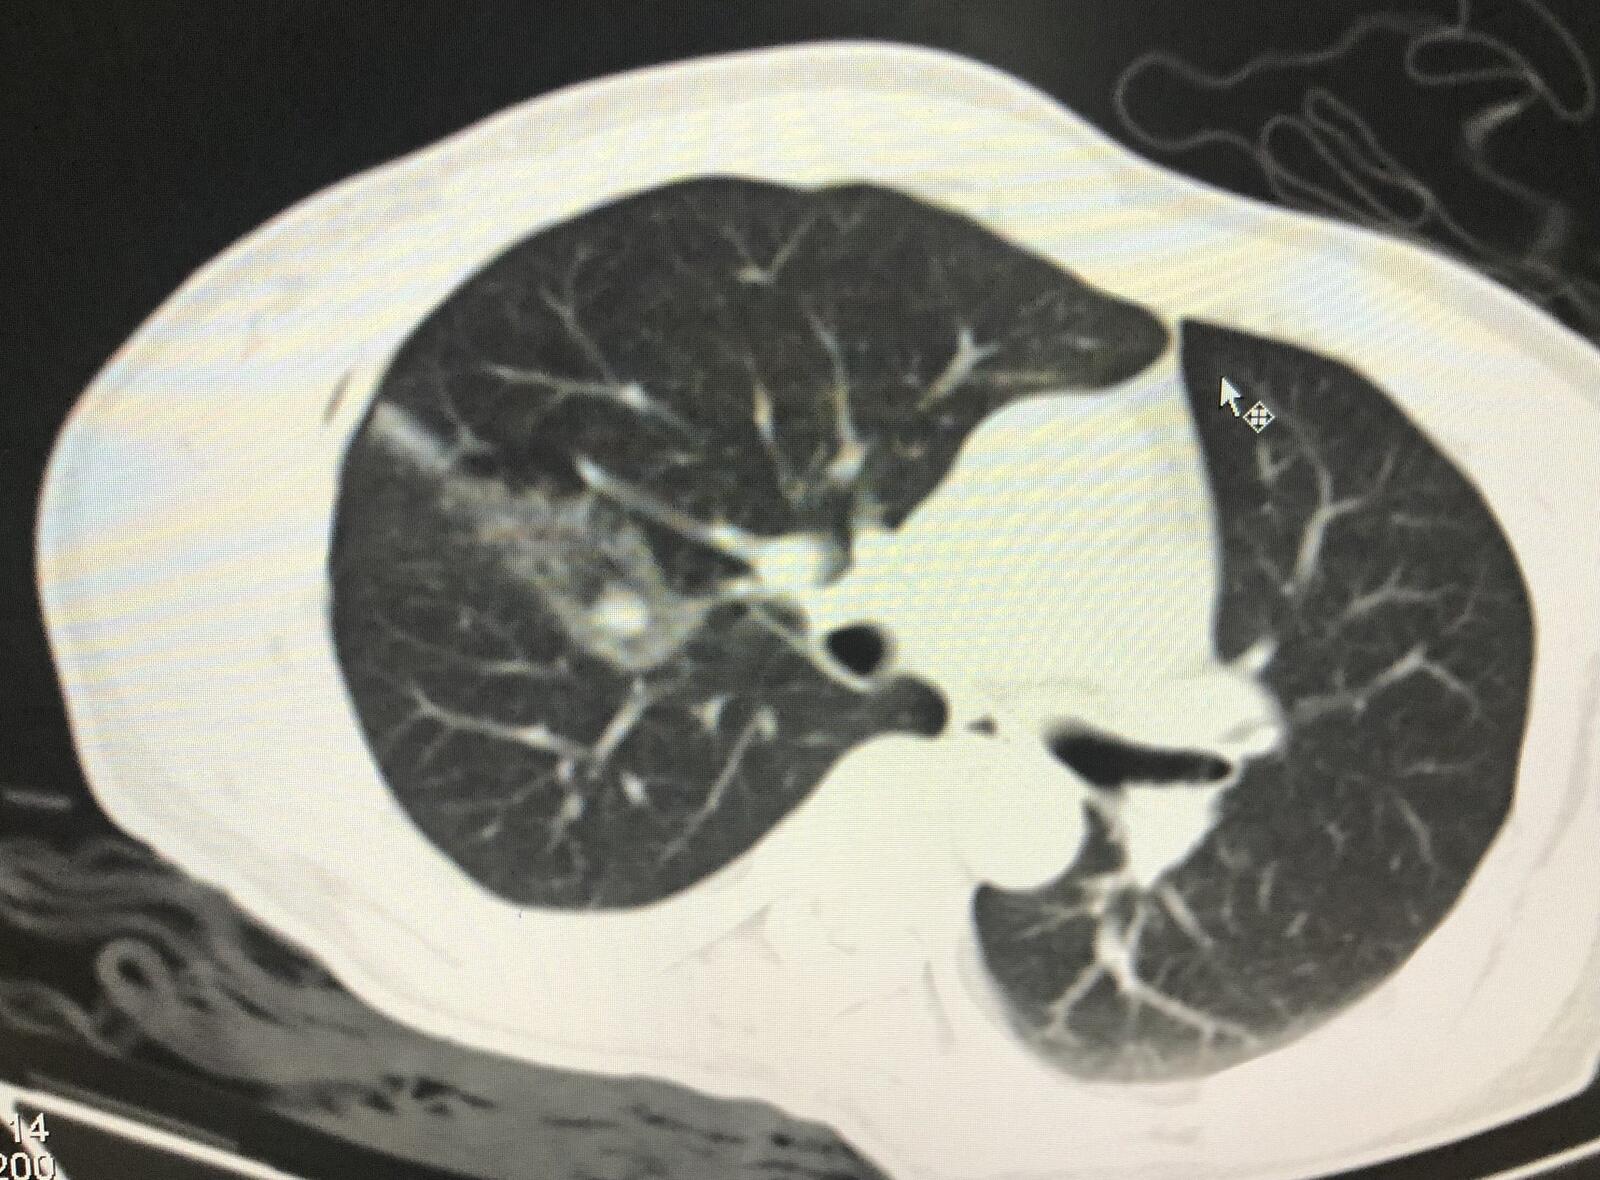

1.患者肝癌术后,出现右肺结节,考虑肝癌肺转移,行微波消融灭活肺部病灶。

右肺结节直径约1厘米